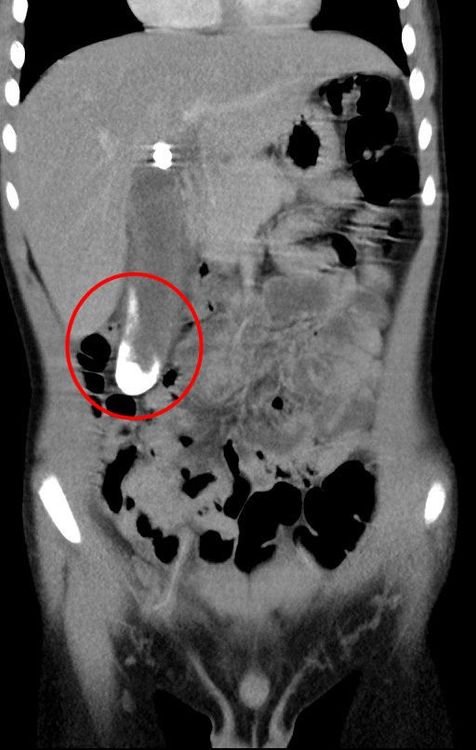

透過超音波與電腦斷層確認,陳小弟的膽囊中有一些細小的結石,考慮孩子並無家族病史,也無常見形成小兒膽結石的危險因子,醫師與家屬討論過後,先使用藥物控制,以內科療法治療,讓結石不要持續增大;直到後續陳小弟再次就醫,發現結石情況並無好轉,甚至已逐漸連成一大片,卡在膽囊管進總膽管處,造成慢性發炎。由於內科治療無法使病況緩解,最後決定開刀。